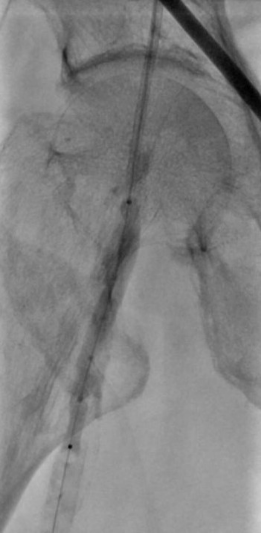

1. 术前造影:

2. 经鞘置入椎管、CXI、V18导丝正向开通股浅动脉下段,导丝通过,导管无法跟进,经皮穿刺钙化灶,导管跟进造影发现位于内膜下。

3. 经皮穿刺胫前动脉上段,置入新V18导丝,跟进CXI,与正向的椎管双向会师,建立导丝通路,予以3.0球囊预扩张。